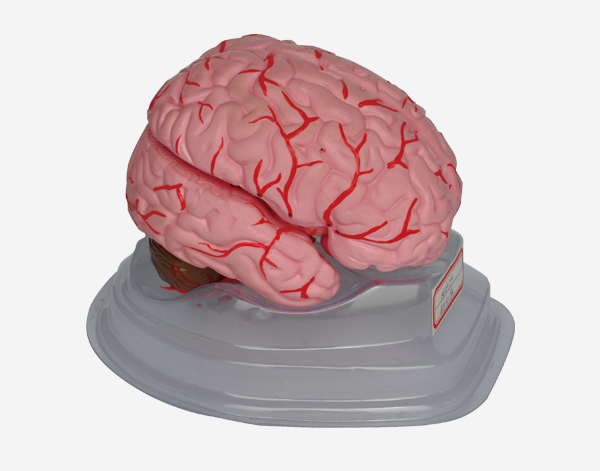

Human Brain With Arteries

Model of Human Brain With Arteries

This model facilitates the medical students to get a correct understanding of the external features of the brain and its arte

rial supply as a whole,as well as the relations between their component portions.External features of the brain:cerebral

hemisphere,brain stem,cerebellum.The arterial supply of the bra inaources,vertebral,internal carotid arteries,arteria supply of the

cerebellum and cerebrum.Made of PVC and can be separated into 7parts,on base.Size(cm):17x17x13